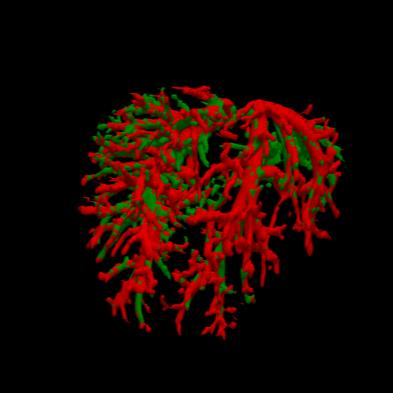

Manually segmenting the hepatic vessels from Computer Tomography (CT) is far more expertise-demanding and laborious than other structures due to the low-contrast and complex morphology of vessels, resulting in the extreme lack of high-quality labeled data. Without sufficient high-quality annotations, the usual data-driven learning-based approaches struggle with deficient training. On the other hand, directly introducing additional data with low-quality annotations may confuse the network, leading to undesirable performance degradation. To address this issue, we propose a novel mean-teacher-assisted confident learning framework to robustly exploit the noisy labeled data for the challenging hepatic vessel segmentation task. Specifically, with the adapted confident learning assisted by a third party, i.e., the weight-averaged teacher model, the noisy labels in the additional low-quality dataset can be transformed from "encumbrance" to "treasure" via progressive pixel-wise soft-correction, thus providing productive guidance. Extensive experiments using two public datasets demonstrate the superiority of the proposed framework as well as the effectiveness of each component.

翻译:将来自计算机地形学(CT)的肝脏船只人工分割,由于船只的低调和复杂形态,由于低调和复杂的形态,造成极端缺乏高质量的标签数据,因此比其他结构更需要专门知识和难度大得多。如果没有足够的高质量的说明,通常的数据驱动的基于学习的方法就会与不足的培训斗争。另一方面,直接引进低质量说明的额外数据可能会混淆网络,导致不良的性能退化。为了解决这一问题,我们提议建立一个新的、由教师协助的、有说服力的、有说服力的学习框架,为具有挑战性的肝脏船只分解任务强有力地利用响亮的标签数据。具体地说,在第三方(即加权平均教师模式)的协助下,经过变通的自信学习后,额外低质量数据集中的噪音标签可以从“阻力”转变为“压力”,通过渐进式的像素方法的软校正,从而提供富有成效的指导。使用两个公共数据集进行的广泛实验,显示了拟议框架的优越性以及每个组成部分的效能。